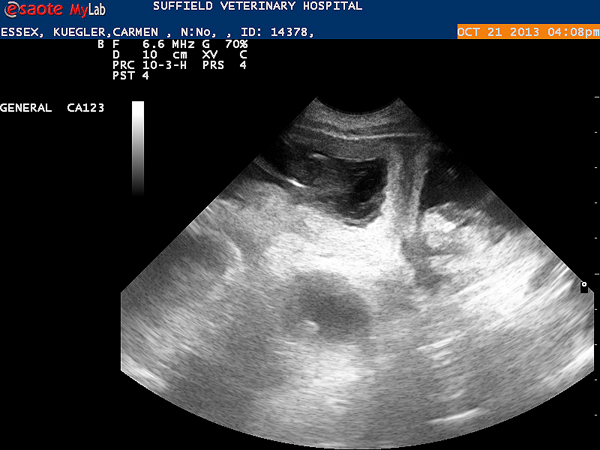

Today, on day 34th after the first mating, we did an ultrasound examination. We are very happy: Essex is pregnant. So, we look forward to her puppies in mid-November.

We could see several fetuses: